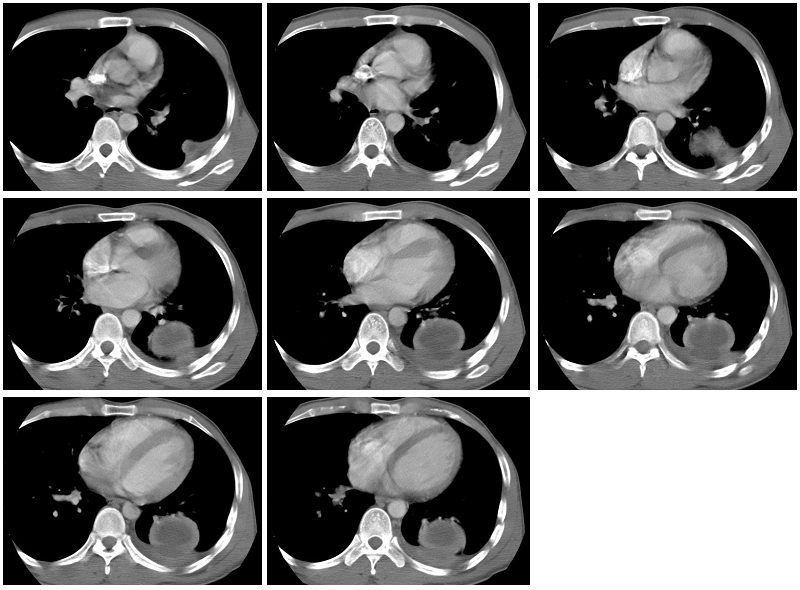

男性,34岁,咳嗽,胸痛一个月,左下肺呼吸音清。分别是肺窗(1-2),纵隔窗(3),增强动脉期(4),平衡期(5),平扫ct值为40-50hu,增强后厚壁达到80-100hu, [/color]

左肺下叶背段肿块影,边缘欠光整,无明显分叶,局部胸膜反应明显,增强扫描明显强化,其内见无强化低密度区,考虑左肺下叶化脓性感染,建议正规抗炎治疗后复查!鉴别诊断:1、结核瘤:环形强化或无强化,周围见卫星灶 2、周围型肺癌:分叶毛刺明显,局部胸膜凹陷征。

类圆形肿块,强化显著,内液化区无强化,考虑左下肺脓肿,左侧少量胸腔积液。

左下肺可见类圆形高密度影,可见双环征,增强后,壁强化明显,内低密度影未见强化,同侧胸腔积液,左下肺脓肿。治疗后复查。